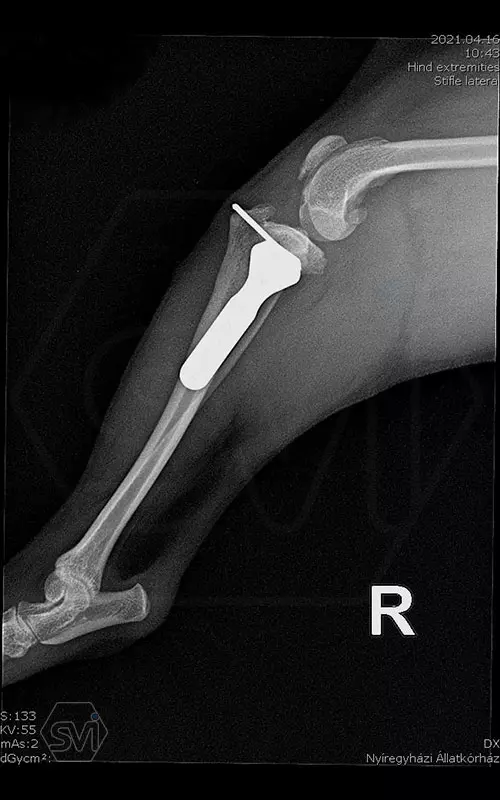

Introducing the TPLO-M „terraced” plate family from Smartvetimplants.com

In small dogs, medial patella luxation (MPL) and the rupture of anterior cruciate ligament (RACL) often occur simultaneously. During the surgical procedure, the joint must be stabilized and the patella fixed in the middle axis at the same time.

The solution of Smatvetimplants is the TPLO-M plate family with terrace:

Between October 2020 and December 2021, we performed 19 TPLO-M surgeries at the Animal Hospital in Nyíregyháza,: 16 times used the mini (2.0 R12) and 3 times the small (2,4 R15) TPLO-M plate.

The experience is very encouraging, we find the system and plates suitable for the simultaneous treatment of MPL and RACL. ( in case of 4/4 pat. lux. also). We will back soon with details.